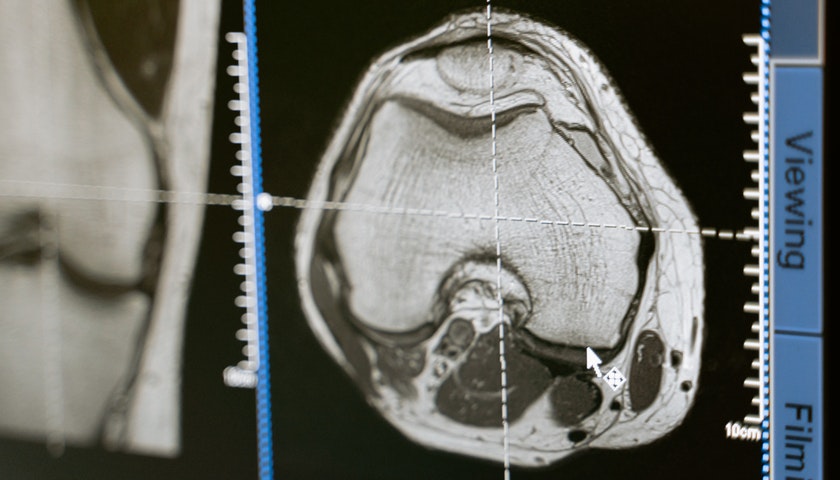

从业务上看,数坤科技主要提供疾病筛查、诊断以及治疗选择与规划的AI医学影像解决方案,并且持续推出行业突破性产品,已有包括数字心、数字脑、数字胸、数字腹、数字肌骨等37款产品。根据灼识报告,按国家药监局医疗器械注册证书数量计,数坤科技在中国AI医学影像公司排名第一。